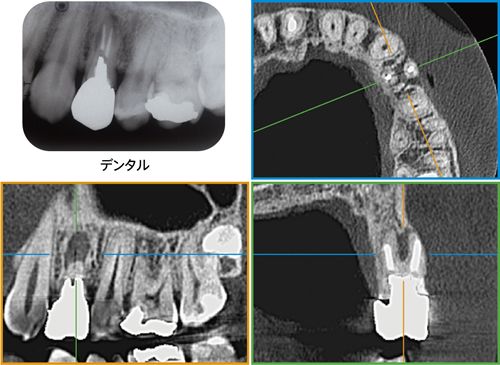

CT画像による診断

CTデータを実際の口腔内模型と合成し、インプラント埋入のシミュレーションを行います。